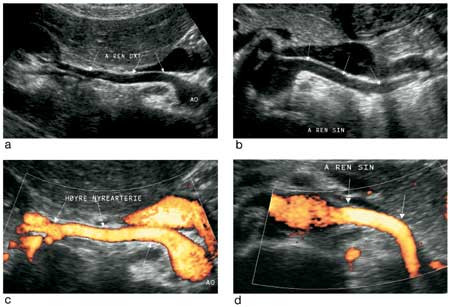

Med pasienten i ryggleie ble så aorta og nyrearterier undersøkt (fig 1). Etter vinkelkorreksjon ble det hentet ut dopplerkurver fra ulike avsnitt av arterien, særlig der det var påvist dopplerdistorsjon (aliasing). Hos alle overvektige har det vært forsøkt å fremstille nyrearteriene med gradert kompresjon og optimal innstilling for høy dopplersensitivitet. Målt maksimal systolisk hastighet (PSV) over 180 cm/s ble tolket som forenlig med signifikant stenose (fig 2). Det ble ikke brukt ultralydkontrastmiddel.

Sentral dopplerundersøkelse bygger på vurdering av blodstrømmen gjennom stenosen, med påvisning av økt hastighet. Systolisk maksimalhastighet (PSV) > 180 cm/s har i mange studier vist seg forenlig med en signifikant stenose i nyrearterien. Sammenliknet med angiografi er det funnet sensitivitet/spesifisitet på 92 % (8).

Perifer dopplerundersøkelse utnytter det faktum at det grunnet trykkfall oppstår forandringer i blodstrømmen perifert for en arteriell stenose (9). Dopplerkurven fra nyrens segmentarterier viser da en typisk parvus-tardus-form (10), grunnet redusert amplitude og forsinket akselerasjon i tidlig systole. Det sistnevnte kan måles som akselerasjonstid (øvre normalgrense 70 ms) (11). Forlenget akselerasjonstid sees kun ved signifikante stenoser, og fortrinnsvis ved stenoser over ca. 75 % (12). Perifer dopplerundersøkelse har den fordel at den kan utføres hos nærmest alle pasienter, uavhengig av adipositas og meteorisme. Studier med perifer dopplerundersøkelse har vist sensitivitet/spesifisitet på over 90 % og undersøkelsestid på rundt 20 minutter (11).